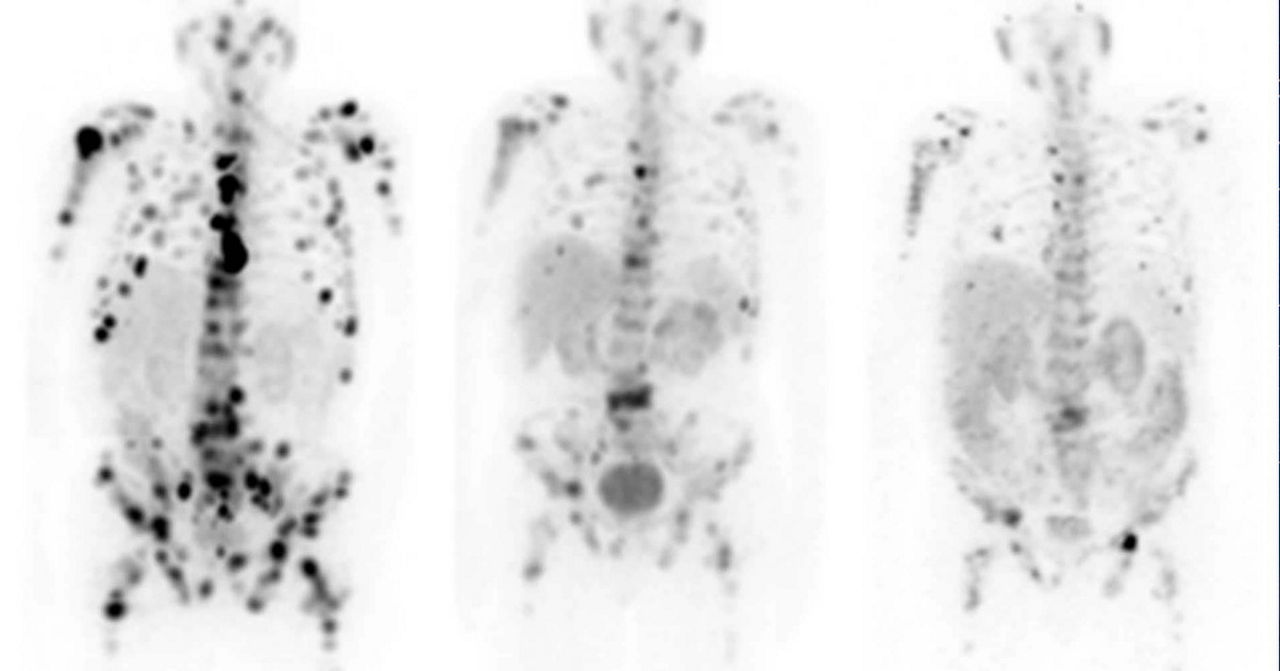

Leveraging transformational imaging technology to realize the promise of precision medicine and help deliver better outcomes. Our medical imaging products range from systems, including MRI, CT, PET, SPECT, Ultrasound, Mammography and X-ray, to digital and AI solutions to help drive healthcare digitialization, help enable faster exam workflow, improve clinical outcomes and increase efficiencies.